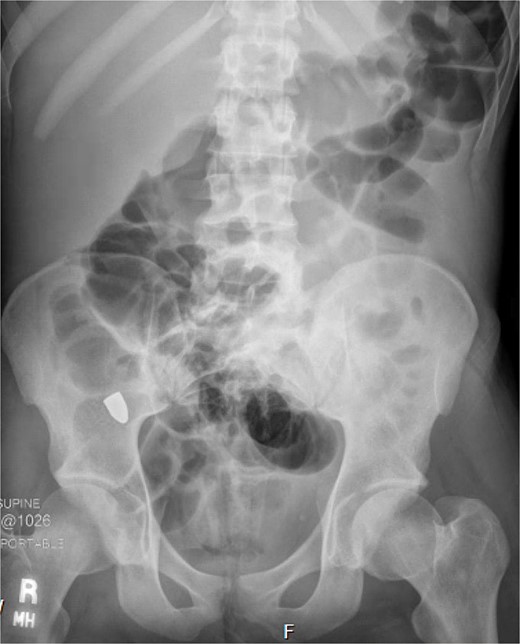

On hospital day (HD) 1, he developed ARDS and required intubation. He became hypotensive, raising concern for mediastinitis, but repeat imaging showed no new findings except that the bullet had migrated below the diaphragm (Fig. 3). Despite his septic appearance, his condition didn’t improve. He was diagnosed with severe AIDS (CD-4 count <100 cells/mm3) and multiple infections (hepatitis A, C, cytomegalovirus, toxoplasmosis, and multi-drug-resistant Pseudomonas pneumonia).

A repeat otolaryngology endoscopy exam on HD 2 revealed a 1.5 cm wound in the posterior pharyngeal wall, confirming the suspicion that the bullet entered the posterior of the mouth, was swallowed, and was now migrating down the GI tract. Serial X-rays tracked its transit (Fig. 4). Despite treatment, his condition remained critical. He underwent tracheostomy, gastrostomy, and diaphragmatic pacemaker placement. The patient was discharged to a long-term care facility on HD 22 but succumbed to complications from AIDS and pneumonia months later.